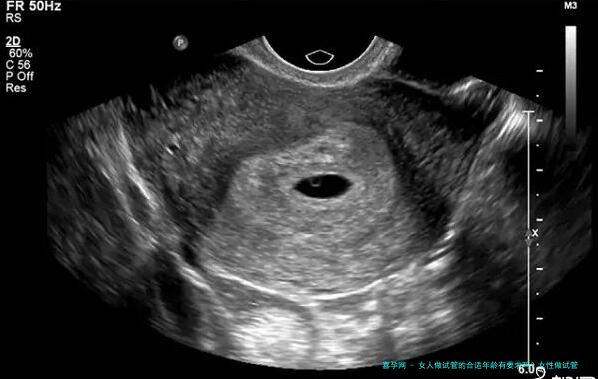

促排卵阶段 (约 10-14 天): 医生会根据患者的身体情况开具药物,刺激卵巢生成多个成熟卵子。这段期间需要定期监测激素水平和卵泡发育情况。 取卵阶段 (约 30 分钟): 在超声引导下,医生通过阴道穿刺的方式取出成熟的卵子。 精液培养阶段 (约 24 小时): 将男方的精液进行处理和培养,以便分离出优质的精子。 胚胎培养阶段 (约 5-7 天):将卵子和精子在实验室中结合受精,形成胚胎。 移植阶段 (约 30 分钟): 将发育成熟的胚胎移植到女性子宫内。移植后,仍旧要进行妊娠检测和按期产检来保证成功怀胎并保障胎儿健康发展。